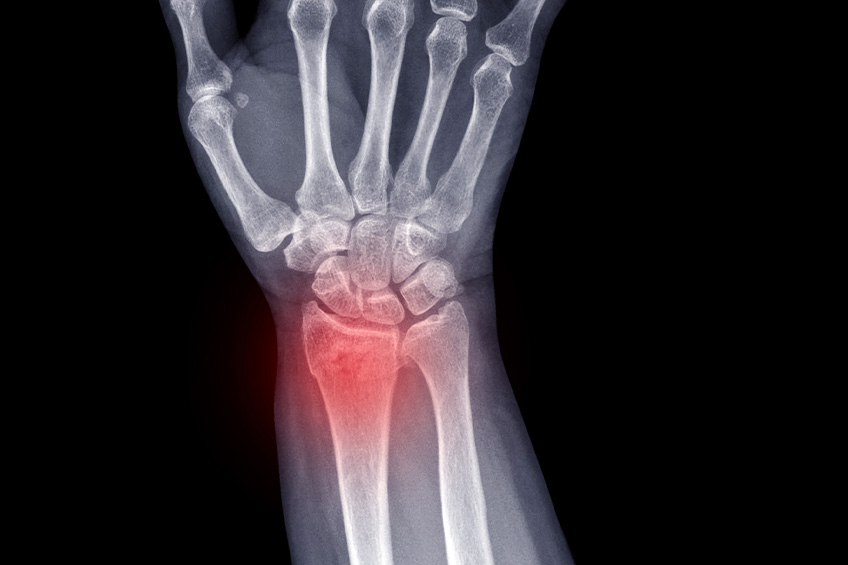

Cals vicieux du poignet

Cette pathologie concerne les suites de fractures du poignet.

Il peut apparaître une gène fonctionnelle liée à des séquelles de fracture du radius distal, traité orthopédiquement ou chirurgicalement.

Celle ci s’exprime par : des douleurs, une raideur articulaire, une gêne esthétique avec déformation le plus souvent en main botte radiale. La gêne fonctionnelle associe également une symptomatologie liée à l’ulna : ulna long avec conflit ulno carpien, gêne à la pronosupination.

En fonction de cette gêne fonctionnelle majeure peut être discuté un traitement chirurgical pour corriger ce cal vicieux.

Plusieurs techniques existent en fonction de la déformation. Il s’agit de recréer une fracture (ostéotomie) pour corriger la déformation : ostéotomie d’ouverture ou de fermeture, avec possibilités d’utilisation de guides de coupe sur mesure pour guider un geste parfait.